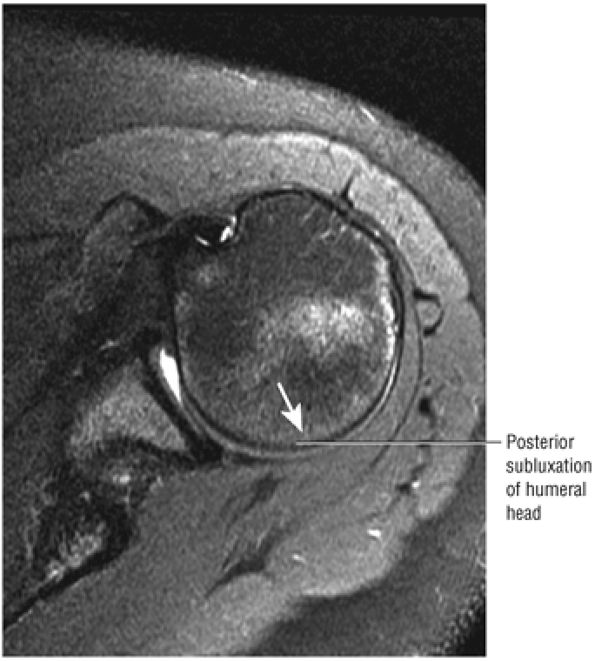

T2* GRE images (10-cm FOV) are used to evaluate intralabral pathology, subscapularis tendinosis, and calcific tendinitis (Fig. 8.3).

FIGURE 8.3 ● Glenohumeral joint contrast on axial T2* GRE image. Axial GRE images optimize visualization of intralabral signal and subscapularis tendinosis. FS FSE images are more sensitive to fluid collections, paralabral cysts, and articular cartilage.